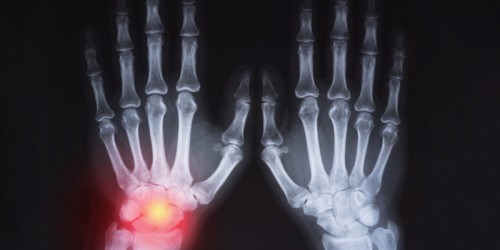

Sometimes when I stand up after sitting, or sometimes just randomly, one of my knees will suddenly hurt badly. It usually goes away within a few hours but it happens many times, at least once a month. I feel the need to maybe pop my knee, but I can't do it. Am I experiencing early signs of arthritis? Do I have a joint problem? This once happened to my thumb and twice to my toe, and it goes away every time I stop moving it. Can I prevent this?